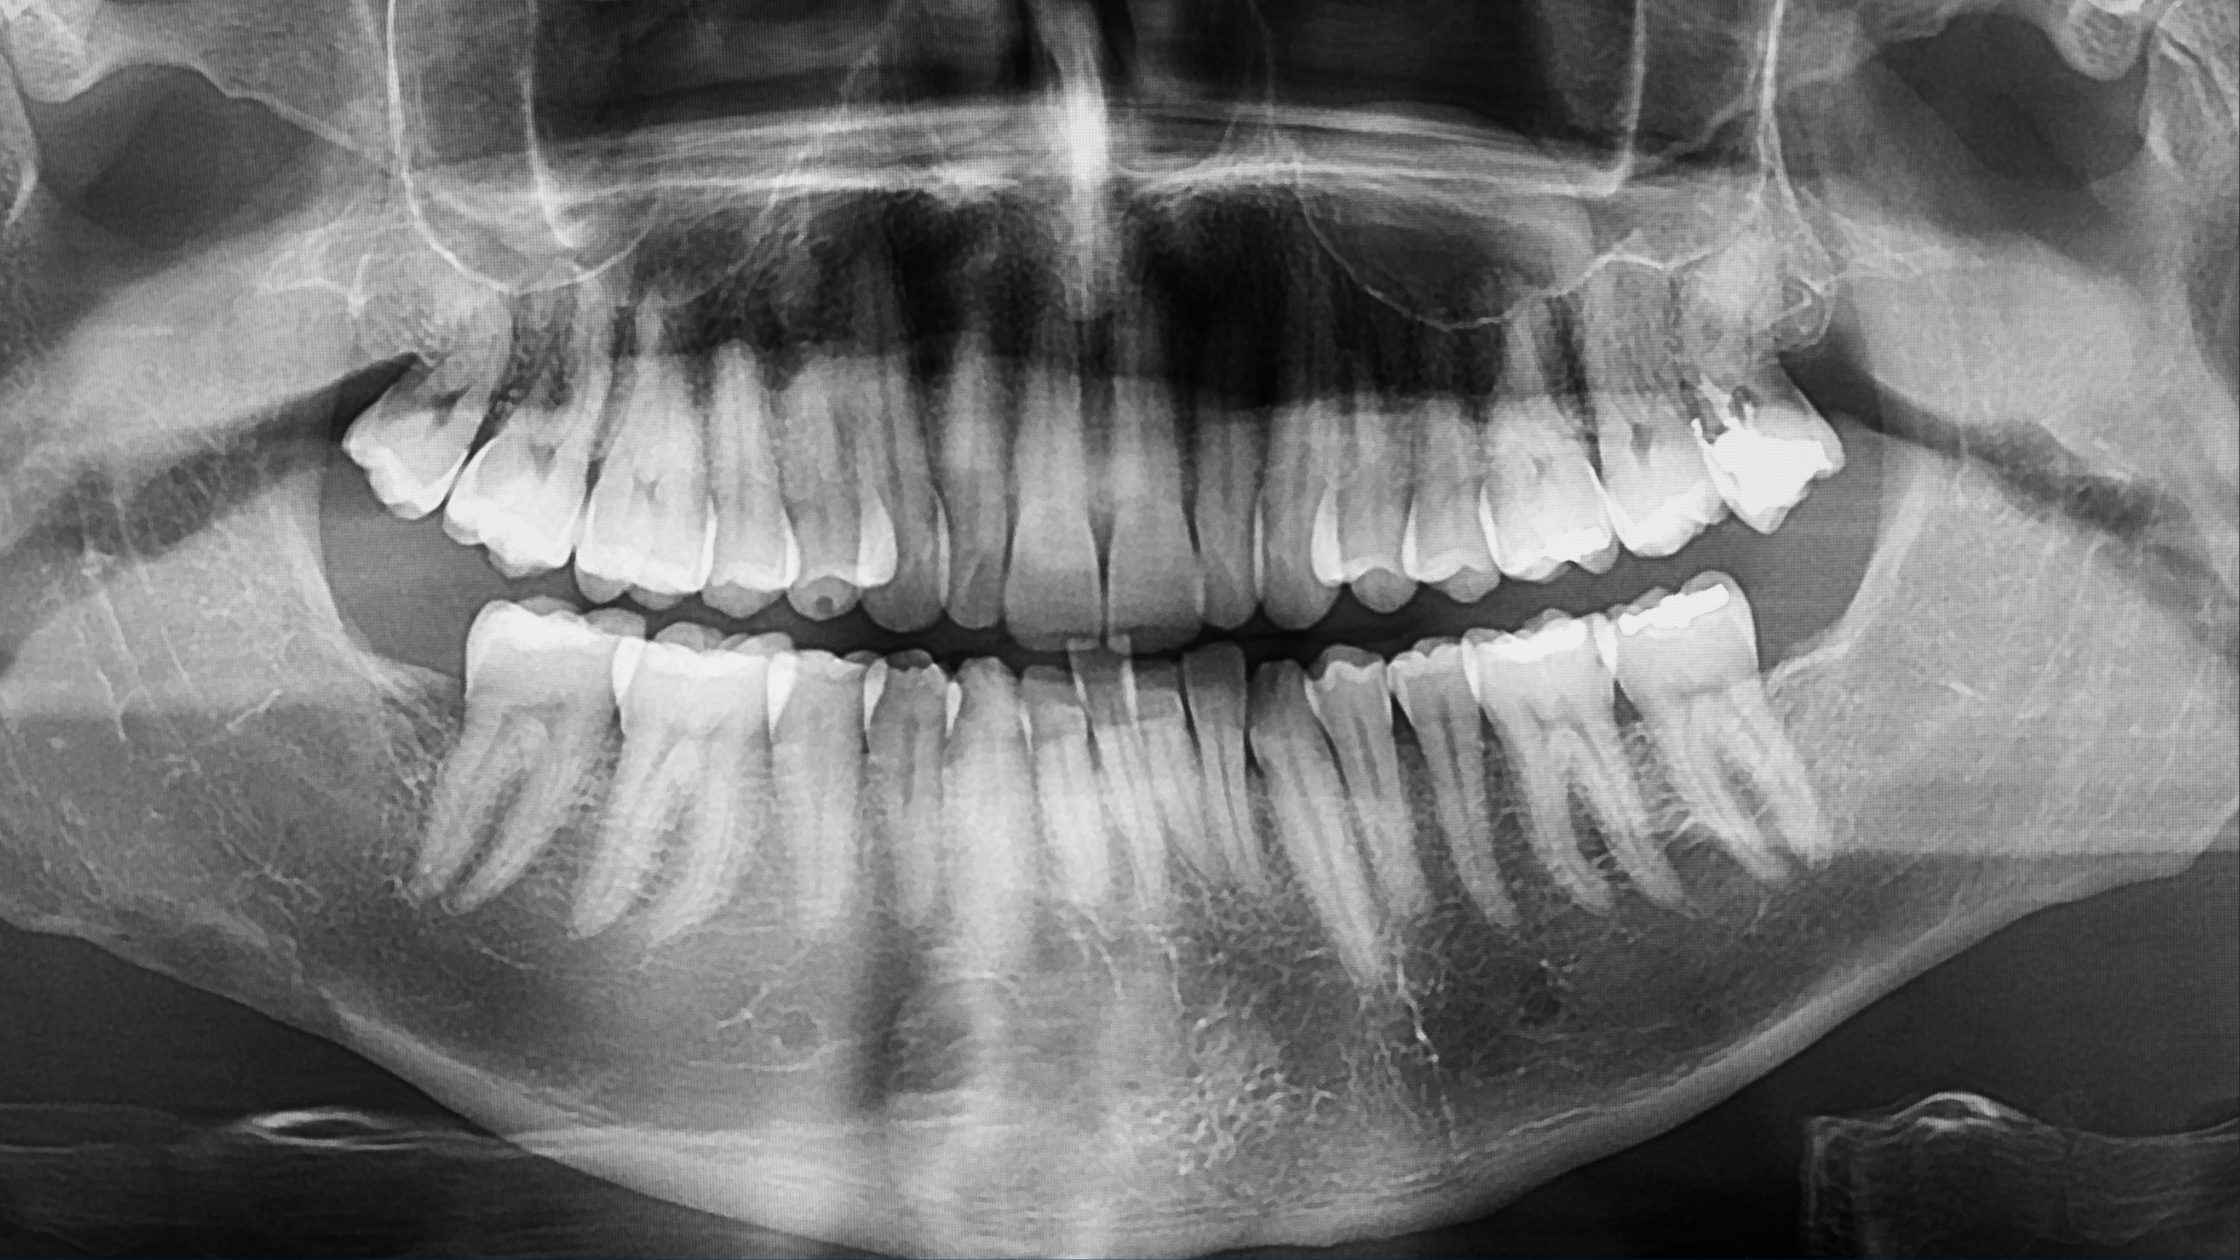

O raio-X panorâmico (ortopantomografia) é um exame que registra toda a arcada dentária em uma única imagem. Ele mostra ossos da face, dentes, articulações e estruturas importantes.

Além disso, o exame é rápido, indolor e oferece uma visão geral completa da cavidade bucal.

Como o exame mostra tudo em conjunto, ele facilita a identificação de problemas que talvez não apareçam em uma imagem isolada.